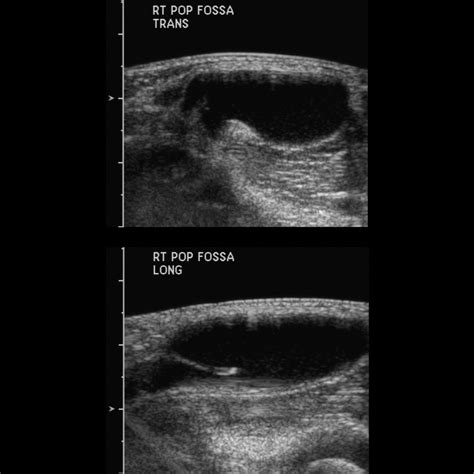

Pediatric Popliteal Cyst | Pediatric Radiology Reference Article | Pediatric Imaging | @pedsimaging

TitlePediatric Popliteal Cyst | Pediatric Radiology Reference Article | Pediatric Imaging | @pedsimaging